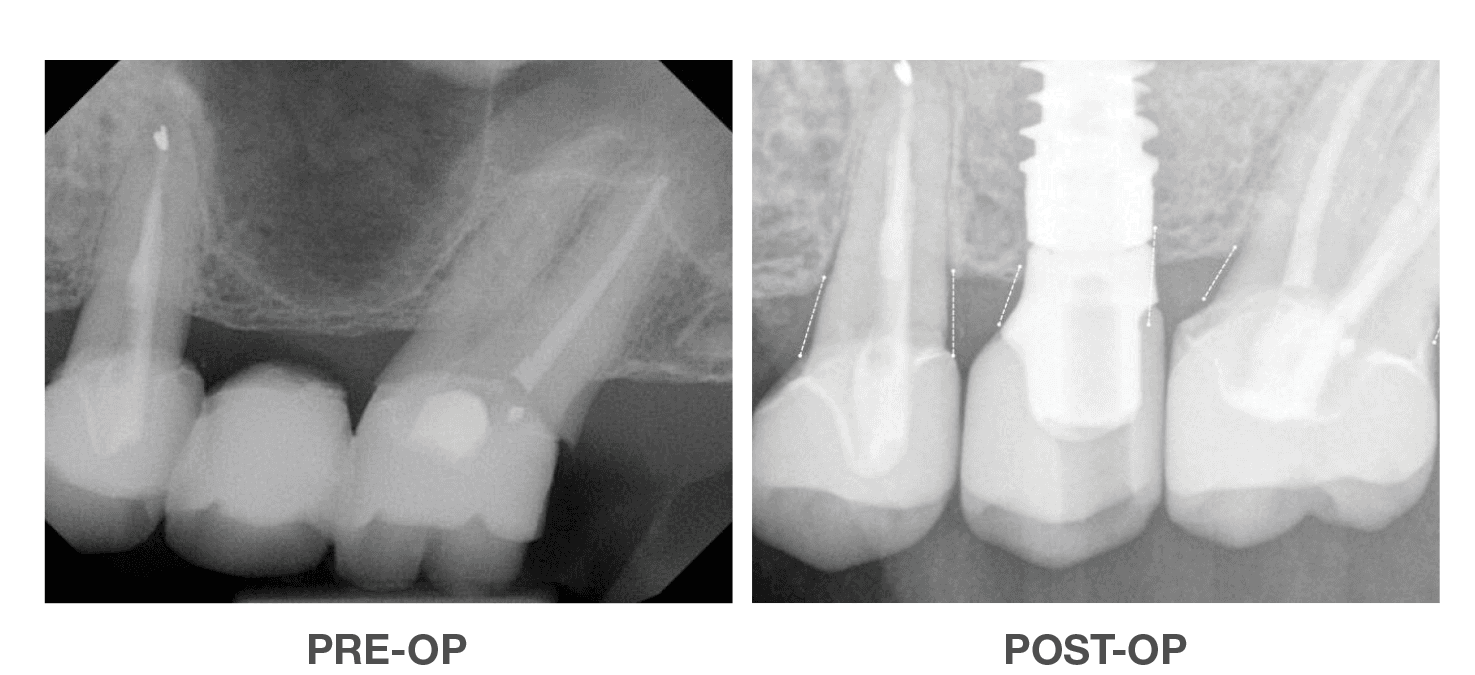

Vertical Ridge Achievement

Using OraGen® Cellular Bone Matrix

Case performed by: Dr. Edgard El Chaar, New York, NY

Horizontal Ridge Achievement

Using OraGen® Cellular Bone Matrix

Case performed by: Dr. Edgard El Chaar, New York, NY

Successful Vertical & Horizontal

Augmentation to Repair Failed Implant

Using OraGen® Cellular Bone Matrix

Case performed by: Dr. Robert Miller, Plantation FL